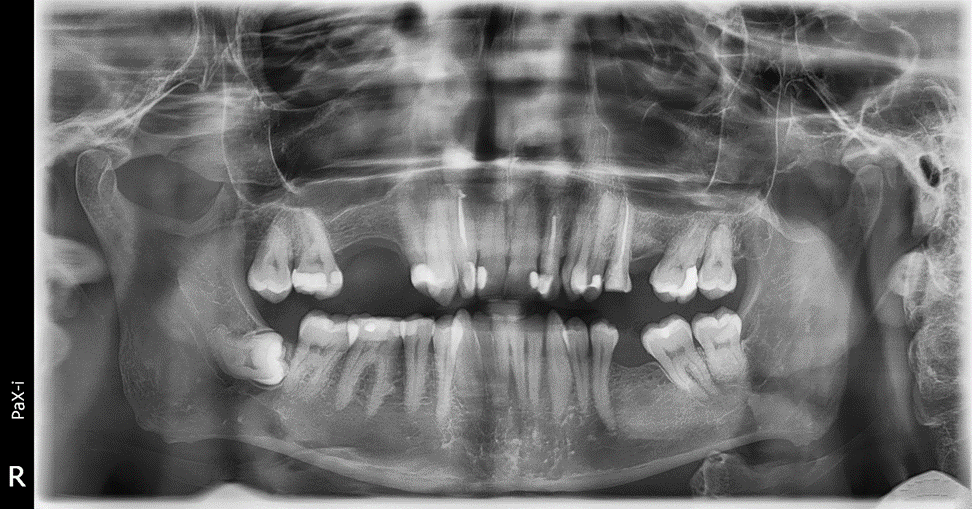

Они самые крайние в зубном ряду и самые последние прорезаются. Чаще всего, зубы мудрости начинают прорезаться, когда уже полностью сформирован постоянный зубной ряд на обеих челюстях, от чего остается критически мало места для полноценного прорезывания и развития восьмых зубов. Именно эта нехватка места и является одним из показаний к удалению зубов. Из-за нехватки места, при активном прорезывании зубов мудрости, ряды сдвигаются, появляется скученность и в боковом и в фронтальном отделах зубных рядов. Восьмерки в данной роли очень коварны, лежат они чаще всего горизонтально или под небольшим углом, и чтобы прорезаться, встать вертикально, им нужно сильно много места для разворота, а такого места совсем нет, поэтому постепенно, под действием 8-к начинают двигаться рядом стоящие зубы к центру, таким образом смещаются и страдают все зубы.

Хуже, если у восьмерок нарушается этап прорезывание. Например, прорезался зуб в сторону щеки, не участвует в жевании, но из-за него часто прикусывается слизистая щеки, от чего происходит частой травме, которая может привести к худшим последствиям. Или же наоборот «ретинированный» зуб,- это значит, что зуб лежит глубоко в кости и не смог прорезаться вообще. В некоторых случаях это может никак не влиять и спокойно пролежать в кости еще долгие годы, но могут и начать со стороны корня разрушать соседние зубы, провоцируя появление кариеса, болезненные воспаления, что приведет так же к подвижности зубов. Поэтому пытаясь переместить зубы с восьмерками по соседству, мы не сможем достичь нужного результата из-за ограничений в движениях.

Поэтому пусть и здоровый зуб мудрости ортодонт рекомендует удалять, так как у данного зуба репутация «бомбы замедленного действия». Пользы в большинстве случаев от 8-х зубов нет, так как в прикус они встают в крайне редких случаях. Конечно, если 8-ка в прикусе и участвует в жевании, здорова и без кариеса, не является причиной сильной скученности ее никто к удалению не порекомендует, но такая ситуация чаще исключение, чем правило.

В большинстве случаев, удаление зубов мудрости, ортодонт рекомендует проводить до начала ортодонтического лечения, ведь это позволит заранее освободить пространство и подготовить челюсть к перемещению зубов. Так же это позволит создать предсказуемые условия для работы брекет-системы или элайнеров.

Есть ситуации, когда восьмые зубы ортодонт может рекомендовать удалять в процессе ортодонтического лечения. Например, если их рост или смещение активизировались под влиянием перемещения других зубов. В таких случаях допустимо удаление зубов мудрости на этапе ортодонтического лечения.

Таким образом, удаление «здоровых» зубов в ортодонтии никогда не принимается легкомысленно. Есть определённые жалобы пациента, конкретные медицинские показания и рекомендации врача ортодонта по достижению того или иного результата лечения. Оно основано на глубоком анализе клинических ситуаций, рентгеновских снимков, компьютерного моделирования и многолетнего опыта.